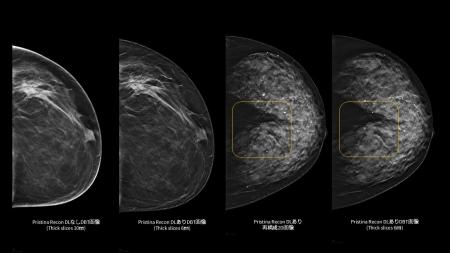

「Pristina Recon DL」で3Dマンモグラフィの視認性を向上

「Pristina Recon DL」は、ディープラーニングと逐次近似再構成技術を活用した、デジタルブレストトモシンセシス(DBT/3Dマンモグラフィ)向けの画像再構成技術です。また、被ばく線量を増加させることなく、高画質で安定したDBT/3Dマンモグラフィ画像の提供を目指します。

さらに、ディープラーニングを用いた高度な画像再構成技術により、アーチファクト(虚像)や視覚的ノイズを低減し、微細構造の視認性を向上させます。これにより、DBT/3Dマンモグラフィおよび再構成2D画像の双方において、読影に必要な情報をより明確に可視化し、診断を支援する読影環境の向上に貢献します。